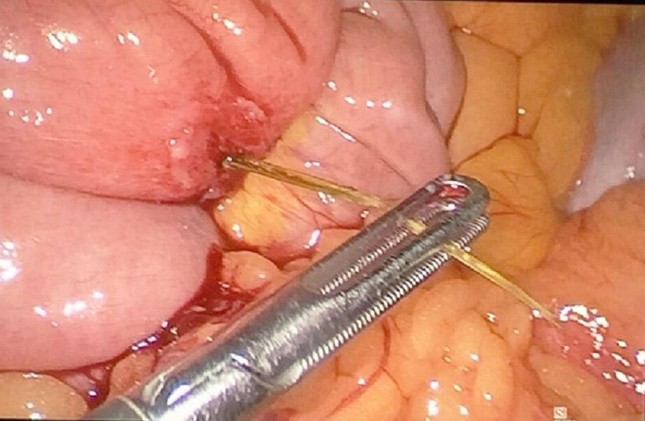

Sau hội chẩn nhanh, các bác sĩ đã quyết định thực hiện cuộc mổ cấp cứu cho người bệnh. BS Dương Phát Minh, khoa Ngoại tiêu hóa, Bệnh viện Nhân dân Gia Định cho biết, chiếc xương cá đâm thủng trực tràng, tạo áp xe cạnh trái trực tràng. Khoang bụng bệnh nhân có nhiều dịch đục, đồng thời khoang sau phúc mạc có nhiều mủ lan từ sau trực tràng đến gốc động mạch mạc treo tràng dưới.

Ê kíp phẫu thuật đã lấy ra chiếc xương cá dài 3cm đồng thời rửa ổ bụng, xử lý nhiễm trùng, rạch tháo mủ ổ áp xe ở cạnh trái hậu môn. Người bệnh được đặt ống dẫn lưu bụng, dẫn lưu cạnh trực tràng và làm hậu môn nhân tạo. Sau hơn 10 ngày điều trị, sức khỏe của bệnh nhân đang dần bình phục.